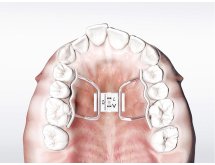

Édition entièrement refondue et riche en nouvelles illustrations, Ursula Wirtz présente les principaux appareils orthodontiques amovibles.

En tant que manuel de travail et d'études, cet ouvrage de référence pour la technique amovible en orthodontie renferme de nombreuses illustrations et constitue une aide précieuse, aussi bien pour le prothésiste dentaire que pour l'orthodontiste.

L'o-atlas II indique de manière précise et concise les aspects à prendre en compte lors de la fabrication d'un appareil orthodontique. Cette édition en français se distingue par sa conception moderne et attrayante.

Plus de 1000 illustrations.